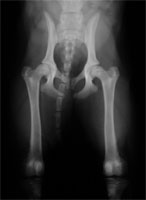

Subluxierende und luxierende Oberschenkelköpfe

Die Autoren der Erstveröffentlichung sind davon ausgegangen, dass bei aus dem Gelenk luxierenden Oberschenkelköpfen die DBO nicht durchgeführt werden dürfe. Sie stelle vielmehr eine Kontraindikation dar. Klinische Erfahrungen mit solchen grenzwertigen Patienten zeigen jedoch, dass Junghunde selbst mit ausgeprägten Subluxationen sehr von der Umstellungsosteotomie profitieren können, weil sich die lockere Gelenkkapsel im postoperativen Verlauf retrahiert und das Gelenk schließlich stabil wird (Abb. 3 a und 3 b). Der Oberschenkelkopf wird zusätzlich mit einem Unterstützungsband (Meij-Technik, Abb. 4) in das rotierte Acetabulum hineingezogen. Zusätzlich hat sich der Einsatz der 40° Platte bewährt. Der im Hüftgelenk nun festen Halt findende Femurkopf übt zudem einen positiven formativen Reiz auf die noch wachsende Pfanne aus, den man als Spreizhosen-Effekt bezeichnet. Als Ergebnis sind stabile Gelenkverhältnisse zu erwarten.

HD luxierte Oberschenkelköpfe

Abbildung 3 a: Vollständig luxierende dysplastische Hüftgelenke

DBO bei luxierten Femurköpfen

Abbildung 3 b: Der selbe grenzwertige Patient nach DBO und Unterstützungsband nach Meij.